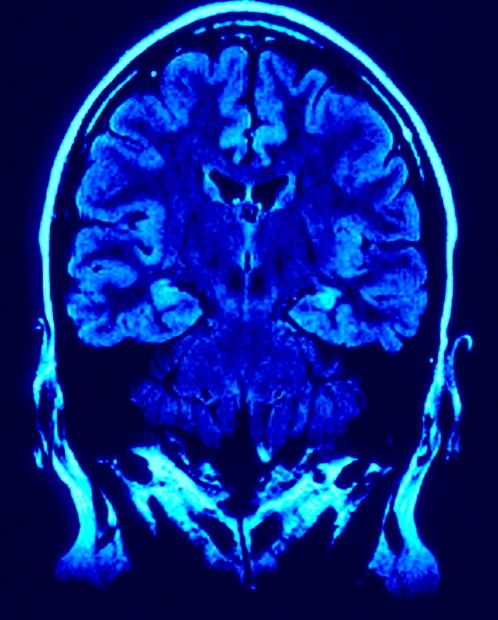

PET/MRi to urządzenie łączące pozytonową tomografię emisyjną z rezonansem magnetycznym. Pierwsze takie urządzenie już pracuje w Centrum Onkologii w Bydgoszczy. Wartość realizacji uruchomienia PET/MRi w Warszawie wynosi około 15-18 mln zł.